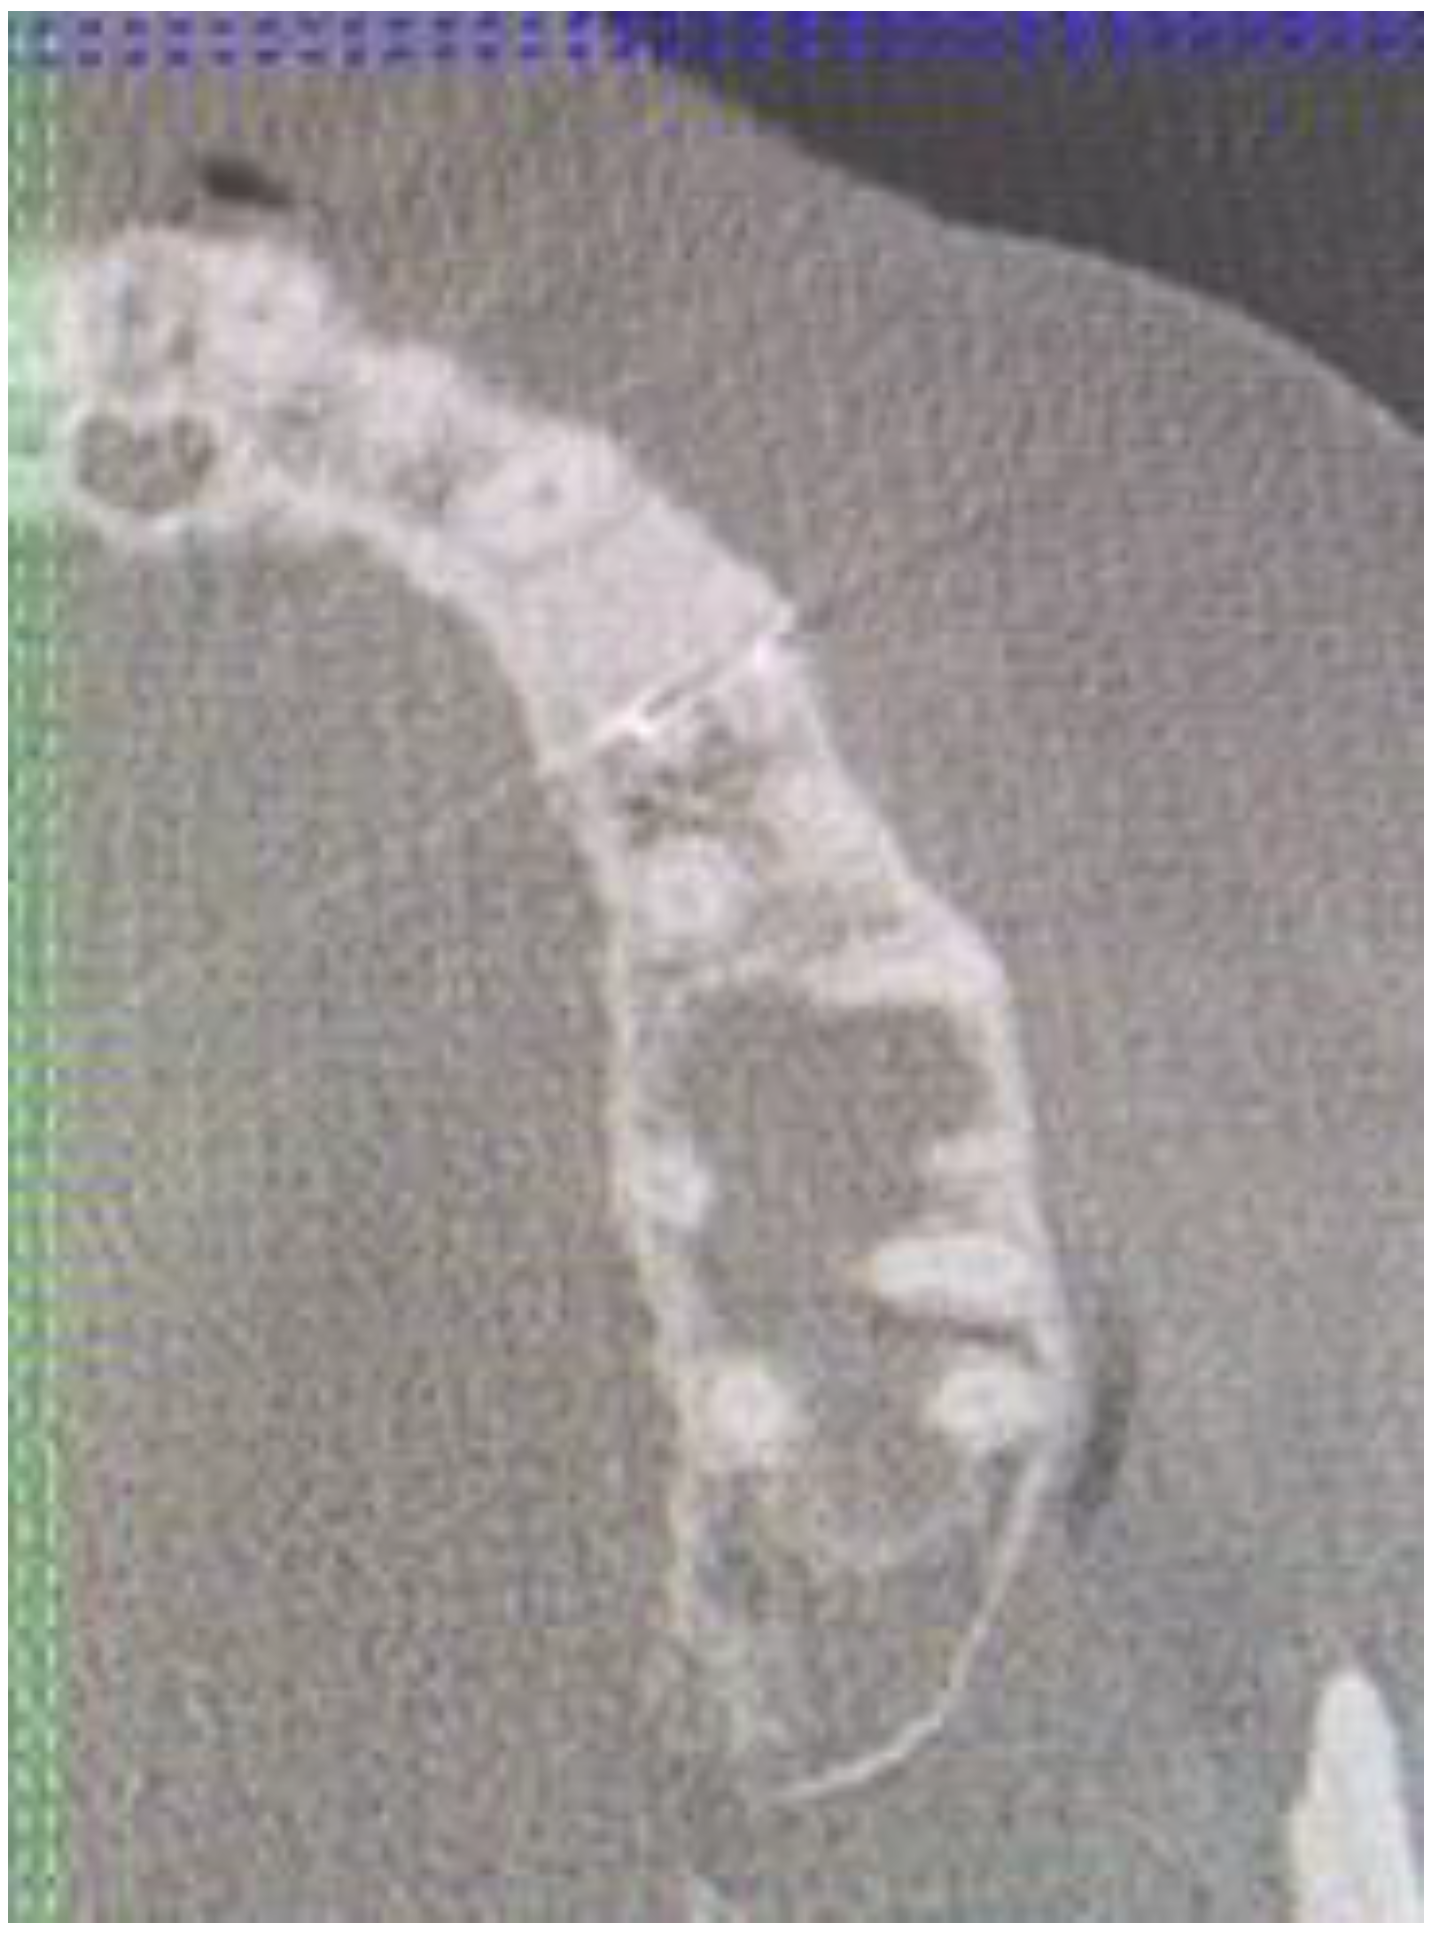

Cone beam computed tomography (CBCT) evaluation revealed the perforation of the buccal cortical bone plate, with expansion towards soft tissues, measuring about 6 mm at longest diameter (Figure 3 and Figure 4). Palatal bone plate remained without any lesions. Because of close proximity to the apex of first premolar and scheduled enucleation with bone curettage/drilling, a decision of endodontic treatment 24 was scheduled. Secondly, such treatment was also indicated because of (1) the loss of cortical plane (possible local aggressiveness of lesion), (2) possible GOC/BOC or other dental-related cyst/tumor occurrence; (3) possible teeth pulp necrosis/inflammation after extensive curettage/bone drilling used for local radicalization protocol; (4) minimizing the time needed for secondary surgery if such would be necessary in case of other pathology. On CBCT further evaluation, a slight sclerotic border close to both tooth apex/roots was visible. Teeth structure remained preserved, with only the buccal cortical bone perforation. On the floor of the left maxillary sinus, a retention mucous cyst was seen; however, due to the clinical irrelevance, only a laryngologist consultation was scheduled.

Figure 3. CBCT sagittal view of LPC.